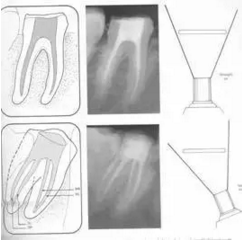

便宜形態(tài)是自切端或咬頜面朝向根尖的直線開擴(kuò)尖錐形態(tài),減少污染物推出根尖孔,方便沖洗、根管充填和側(cè)壁施壓。

保持形態(tài)是根尖狹窄部內(nèi) 1 — 2mm 的一段距離,由擴(kuò)大器回轉(zhuǎn)切割而不貼根管壁提拉切割制成,是擴(kuò)大器的原始形態(tài)(近似平行)。在測試主牙膠尖時給測試者有一個牽引抵抗 (tugback) 的感覺。

抵抗形態(tài)是根管預(yù)備的根尖形態(tài),它是由擴(kuò)大器或根管銼尖端 75 度角自然切割而成。其目的是防止根管充填材超出根尖孔,并且使根尖封閉更加嚴(yán)密。

左圖為正常開髓孔的大小和位置。左邊圖為下顎,右邊圖為上顎。

( 1 )直線通路:根管治療時需要一個直線通路,直線通路能夠達(dá)到根尖三分之一

測量標(biāo)準(zhǔn):以允許根管器械直線并直接進(jìn)入根尖 1/3 且不接觸冠方各壁為標(biāo)準(zhǔn)。

( 2 )髓腔其他改變:如髓室頂、繼發(fā)性牙本質(zhì)、修復(fù)性或增齡性牙本質(zhì)。見左圖。

右圖中有繼發(fā)性牙本質(zhì),切削后獲得直線通路。